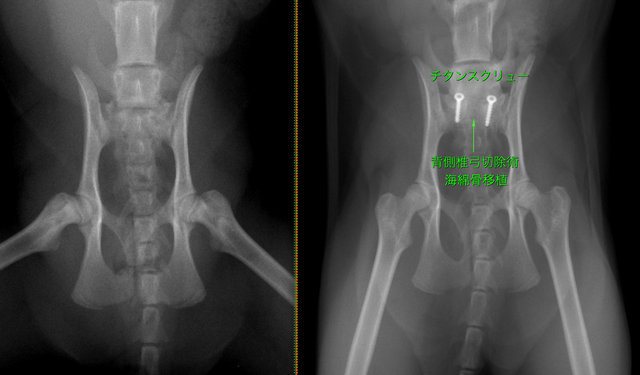

症例はベントラルスロットと腹側固定術と背側椎弓切除により減圧術を行っています。

腰仙椎固定術(不安定症・脱臼・骨折)

L7 骨折